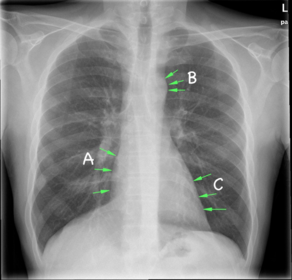

Benævn de markerede strukturer: A: Atrium Dextrum B: Arcus Aortae C: Ventriculus sinister